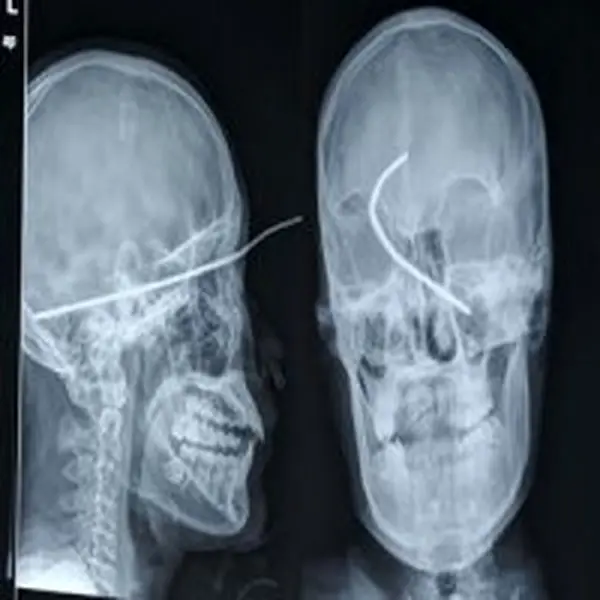

در یک سی تی اسکن ریه حدود 120 برابر یک رادیو گرافی قفسه ی سینه اشعه ایکس جذب بیمار می شود.

جعفری گفت: در اهمیت ثبت وکنترل دوز جذبی مردم باید بگویم که طی تحقیقی که درسال 2007 در آمریکا صورت گرفته است ازمیان 70 میلیون سی تی اسکن صورت گرفته که تحت آزمایش با اشعه ی ایکس قرار گرفته اند 2900 انواع سرطان در سال بعد از آن به واسطه پرتو گیری ها از این سی تی اسکن ها گزارش شده است واین نشان می دهد ما باید مراقبت جدی کنیم.برای ورود به کانال تلگرام ما کلیک کنید.